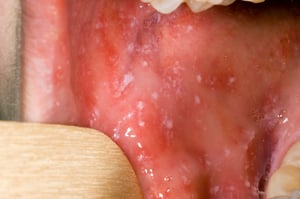

Bevor der Ausschlag beginnt, können Koplik-Flecken im Mund auftreten. Koplik-Flecken sind winzige hellrote Flecken mit einem weißen oder bläulich-weißen Zentrum. Diese Zentren in den Flecken können Sandkörnern ähneln.

Koplik-Flecken sind hellrote Flecken mit einem weißen oder bläulich-weißen Zentrum, die Sandkörnern ähneln. Sie können überall im Mund bei Personen auftreten, die an Masern erkrankt sind.